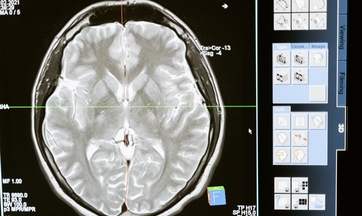

Отделение нейрохирургии в ДГКЮ им. Башляевой

Сложно представить, что чувствует родитель, когда узнаёт, что у его ребёнка опухоль мозга. 4-летняя Аня попала в детскую больницу имени Башляевой. Врачи клиники сделали всё возможное, чтобы малышка снова могла ходить.